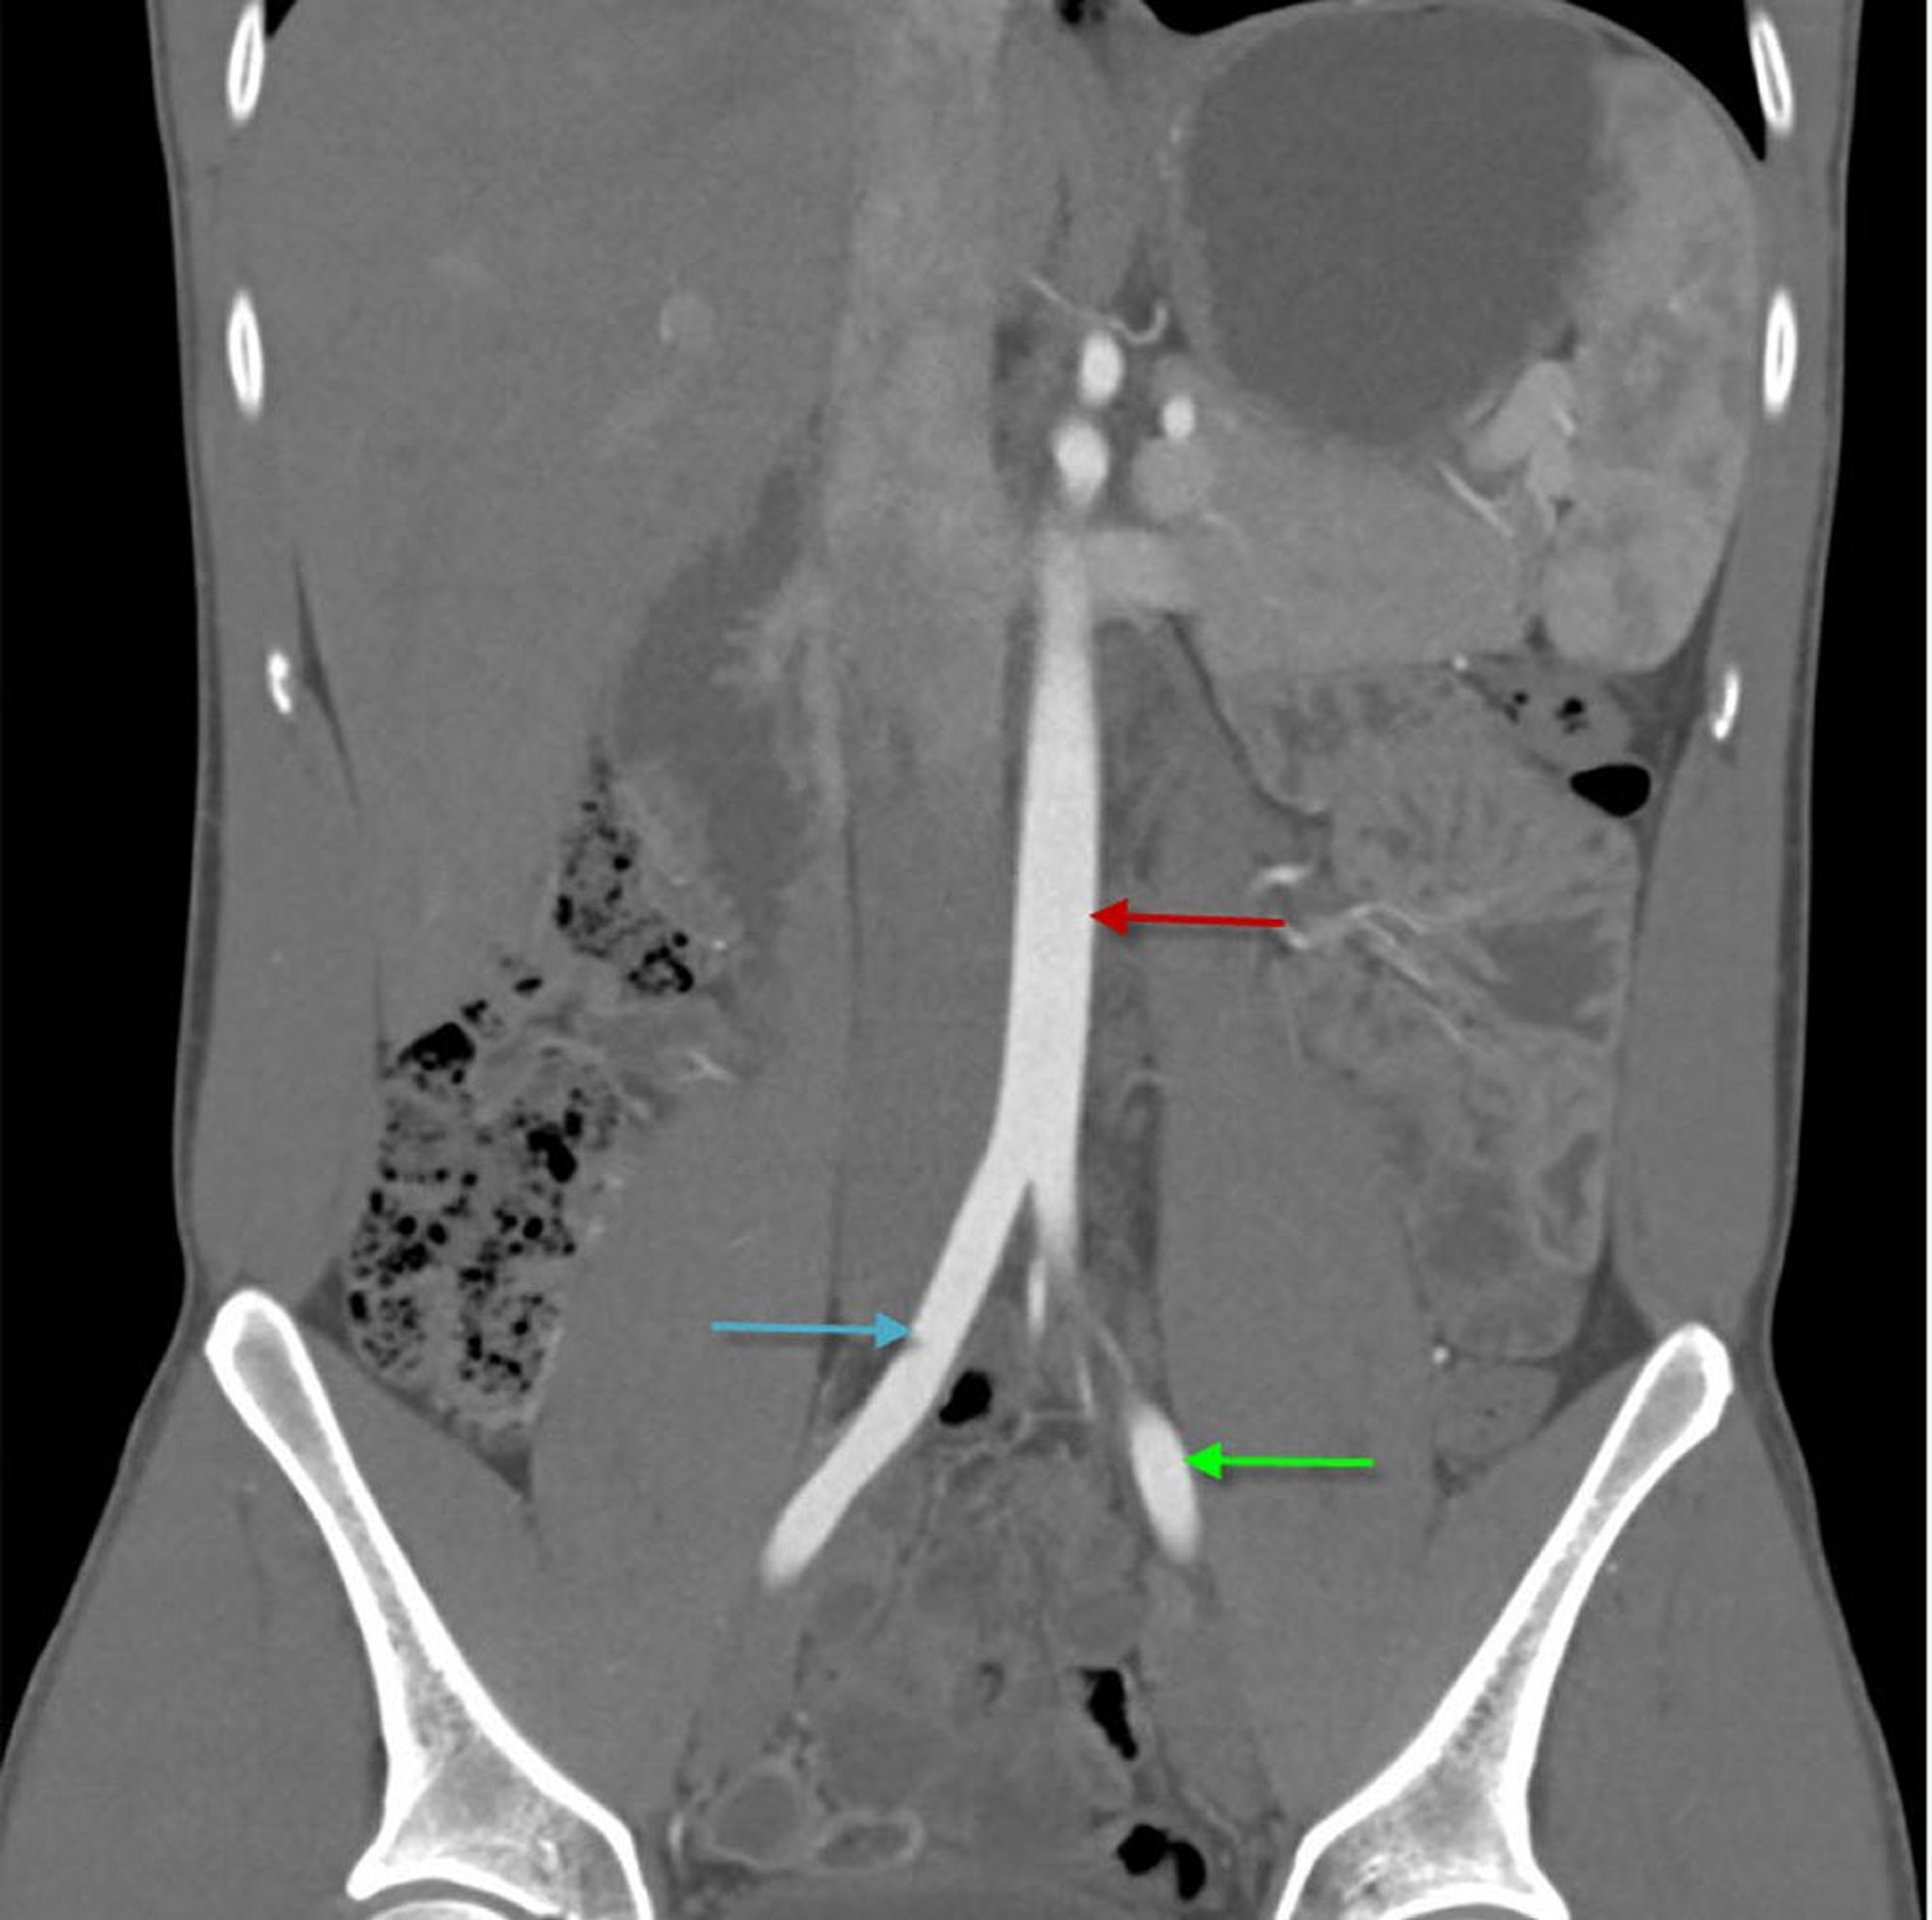

Angio-TC (vista coronale) che mostra l'aorta addominale

Questa immagine mostra l'aorta addominale (freccia rossa) che si divide nelle arterie iliache comuni destra (freccia blu) e sinistra (freccia verde).